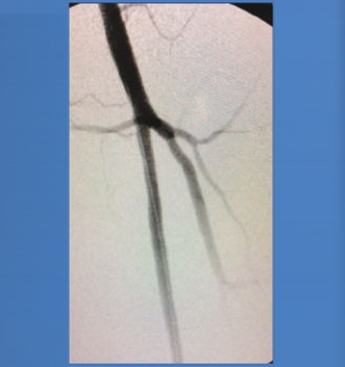

Clinical Case, SFA Lesion

PREPOST